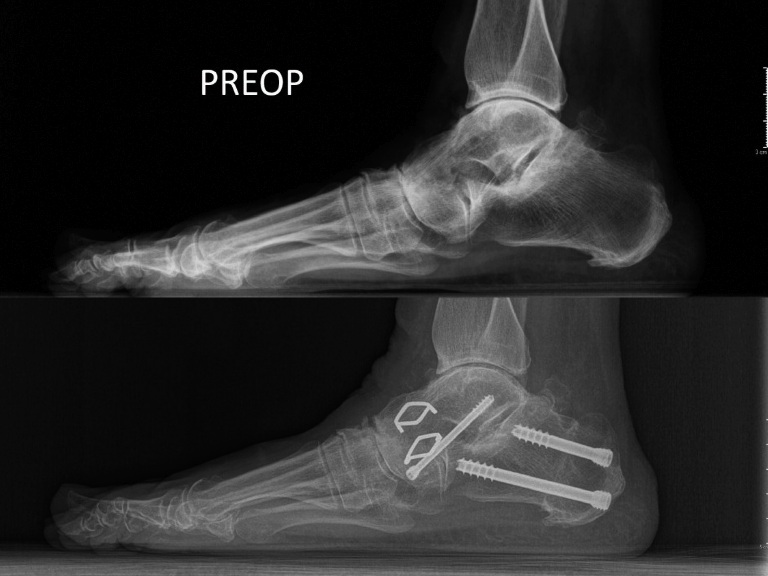

Las artrodesis consiguen el mismo efecto, pero con el bloqueo de una articulación artrósica y/o insuficiente. El restablecimiento del mecanismo anticolapso puede realizarse bloqueando uno o más de un segmento del arco, según la localización del ápex del colapso, desde el hallux a la subastragalina (Figura 4). Una vez restablecida la arquitectura de un buen arco medial, las partes blandas suelen mejorar de manera progresiva y espontánea y suelen también dejar de ser causa del dolor.

Figura 4. En las radiografías en proyección lateral en carga que se presentan se puede observar un colapso del arco medial por una artrodesis talonavicular con excesivo valgo (arriba), antes de una cirugía de rescate. En la imagen de abajo se muestra la misma proyección un año después de la cirugía de rescate con una osteotomía reartrodesis talonavicular y una osteotomía varizante del calcáneo. Es interesante observar cómo, cuando se corrige adecuadamente la altura del arco plantar a cualquier nivel (aquí en el retropié), el arco completo gana altura y las articulaciones vecinas (véase la naviculocuneana) se descomprimen para mostrar una simetría articular.